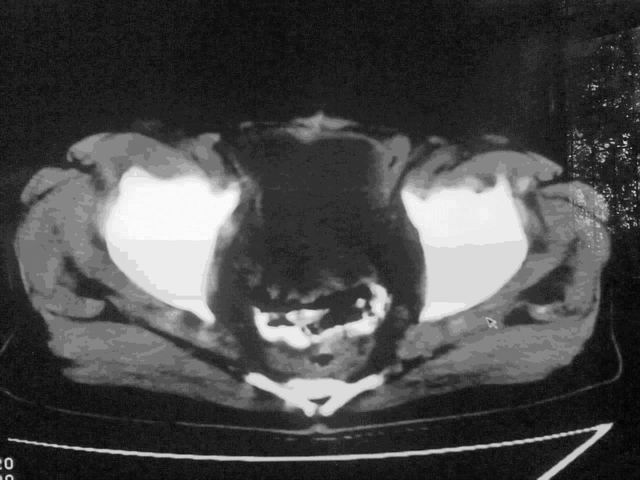

我这个考考大家眼力,看看是升结肠ca还是降结肠ca

下面的是4小时后的,

好象是横结肠占位肝转移,胰头占位?【伙计,您的片也真够意思】

伪影太多,考虑降结肠癌伴肝转移,胆囊炎

伪影太多,考虑升结肠癌伴肝转移,胆囊炎

片子质量差了点,好像是降结肠

考虑升结肠癌伴肝转移;胆囊炎。

结肠占位并肝及腹膜后淋巴结转移。

明确考眼力!考虑降结肠癌伴肝转移可能性。

考虑升结肠癌伴肝转移;胆囊炎

伪影太多,考虑降结肠癌伴肝转移,胆囊炎。